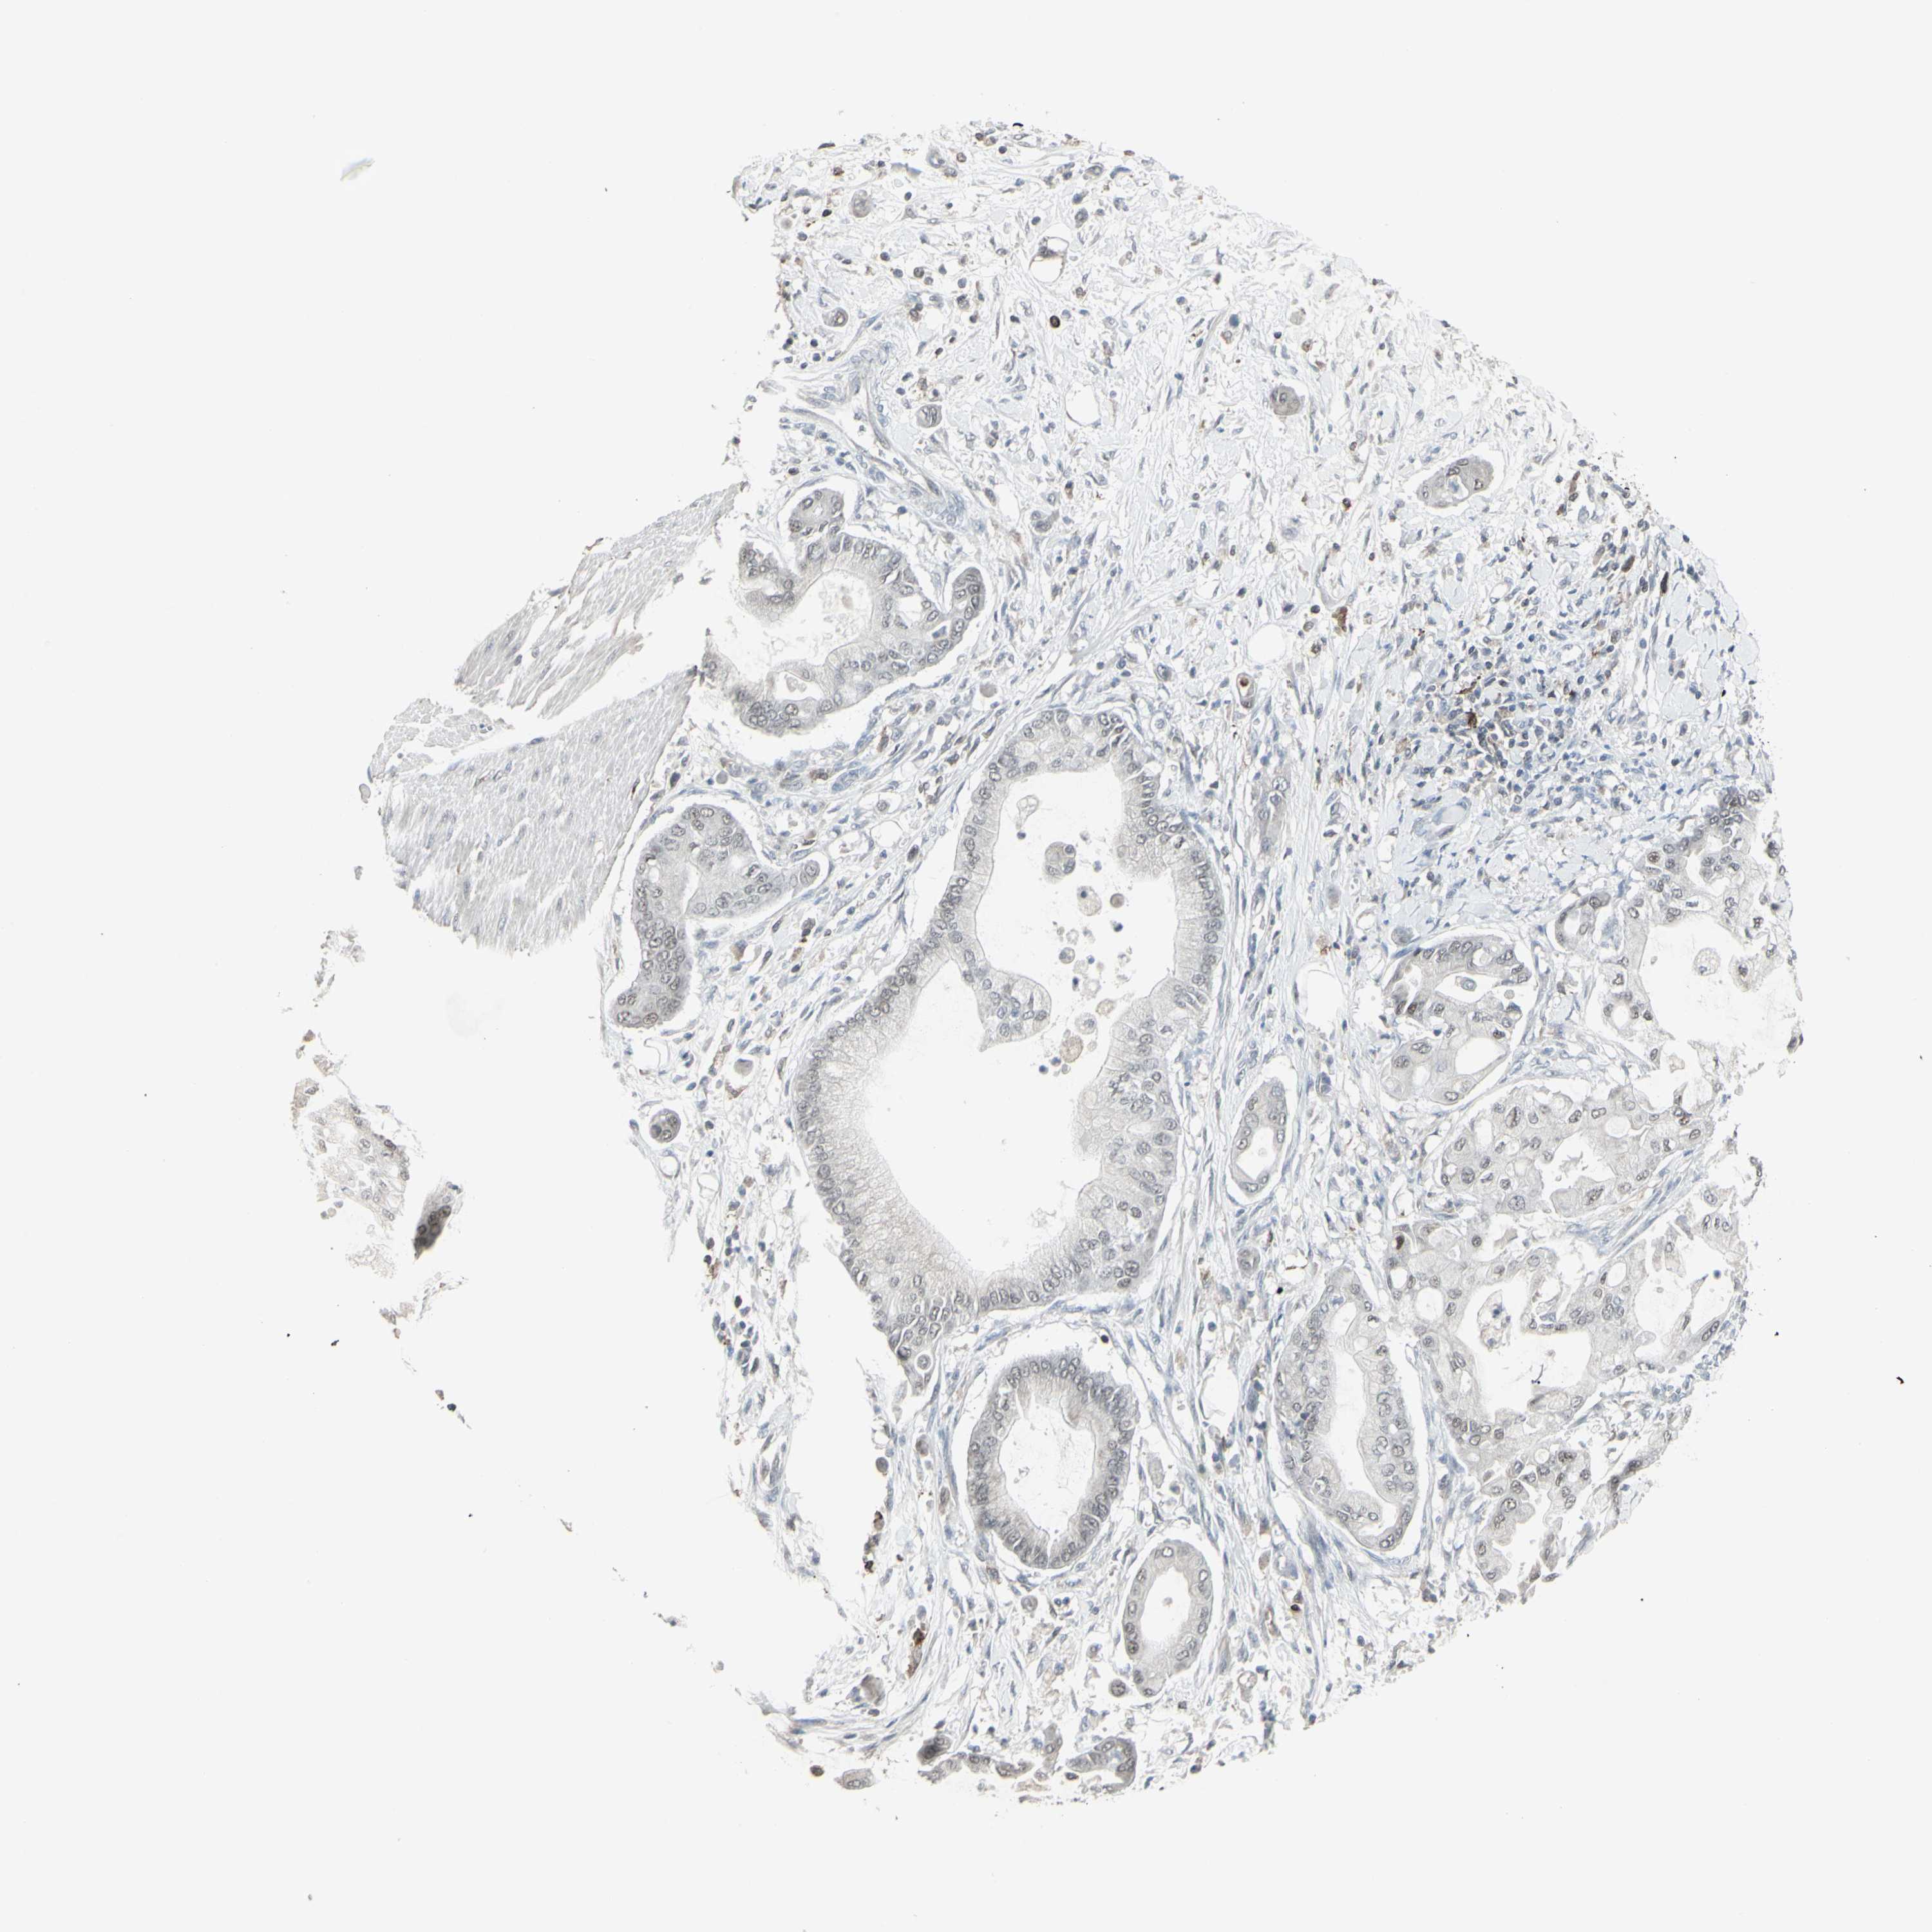

PANCREATIC CANCER - Protein expressioni

A mouse-over function shows sample information and annotation data. Click on an image to view it in a full screen mode. Samples can be filtered based on level of antibody staining by selecting one or several of the following categories: high, medium, low and not detected. The assay and annotation is described here.

Note that samples used for immunohistochemistry by the Human Protein Atlas do not correspond to samples in the TCGA dataset.

Antibody stainingi

Antibody staining in the annotated cell types in the current human tissue is reported as not detected, low, medium, or high, based on conventional immunohistochemistry profiling in selected tissues. This score is based on the combination of the staining intensity and fraction of stained cells.

Each image is clickable and will lead to virtual microscopy that enables deeper exploration of all samples and also displays staining intensity scores, fraction scores and subcellular localization as well as patient and tissue information for each sample.

Antibody HPA010645

Antibody HPA017055

Antibody HPA046639

Staining

High

Medium

Low

Not detected

Intensity

Strong

Moderate

Weak

Negative

Quantity

>75%

75%-25%

<25%

None

Location

Nuclear

Cytoplasmic/membranous

Cytoplasmic/membranous,nuclear

Adenocarcinoma, NOS

Adenocarcinoma, metastatic, NOS